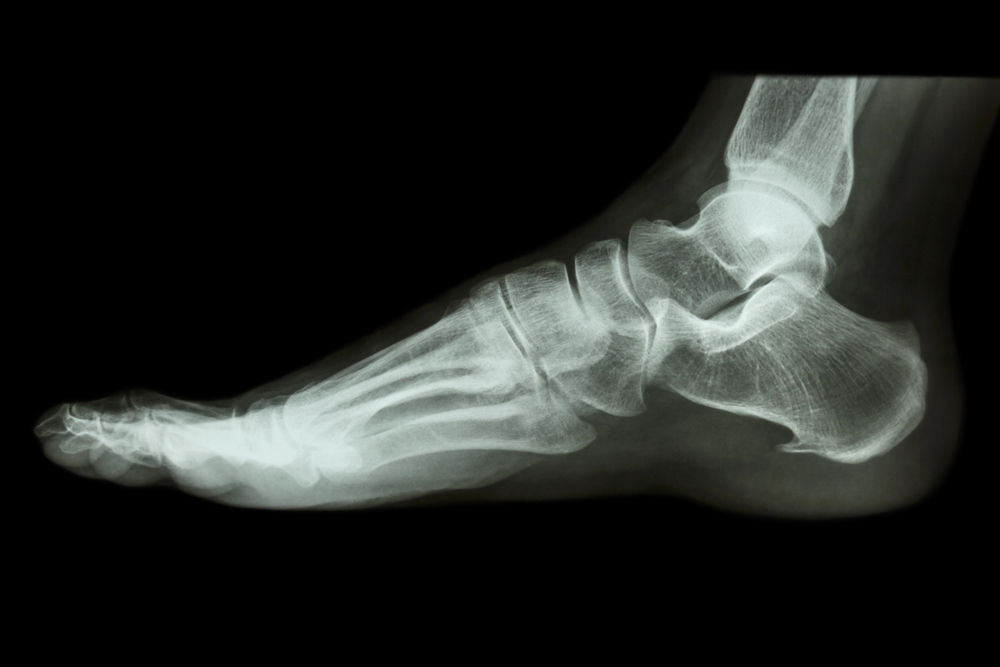

The calcaneus and other weightbearing bones in the lower leg and foot are vulnerable to stress fractures due to repetitive forces that can damage bone microscopically. A stress fracture is difficult to diagnose in its early stages because X-rays lack sensitivity and symptoms can be confused with other conditions such as plantar fasciitis.